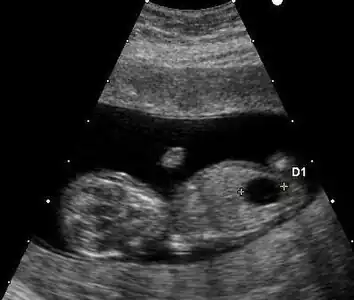

Ultrasound

Prenatal ultrasound can be used to screen for Down syndrome. Findings that indicate increased chances when seen at 14 to 24 weeks of gestation include a small or no nasal bone, large ventricles, nuchal fold thickness, and an abnormal right subclavian artery, among others.[101] The presence or absence of many markers is more accurate.[101] Increased fetal nuchal translucency (NT) indicates an increased possibility of Down syndrome picking up 75–80% of cases and being falsely positive in 6%.[102]

Ultrasound of fetus with Down syndrome showing a large bladder

Enlarged NT and absent nasal bone in a fetus at 11 weeks with Down syndrome